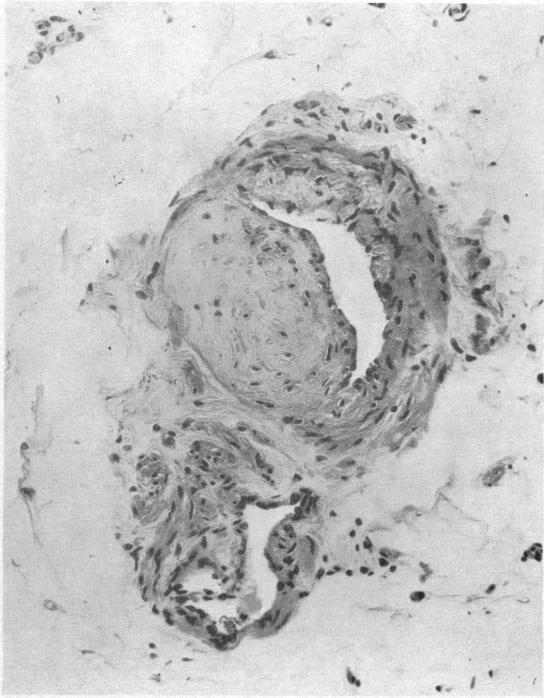

PERIPHERAL NEUROPATHY IN RHEUMATOID ARTHRITIS.

Br Med J. 1965 May 1;1(5443):1141-7. doi: 10.1136/bmj.1.5443.1141.